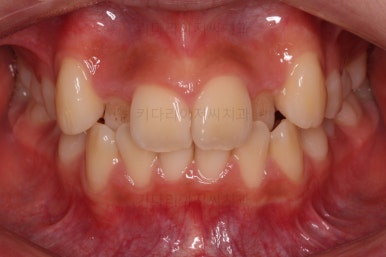

연산동치과 초진 시, 입안의 모습입니다.

보시다시피 앞니쪽이 많이 삐뚤고요. 어금니쪽이 긴밀하지 못한 부정교합이 있네요.